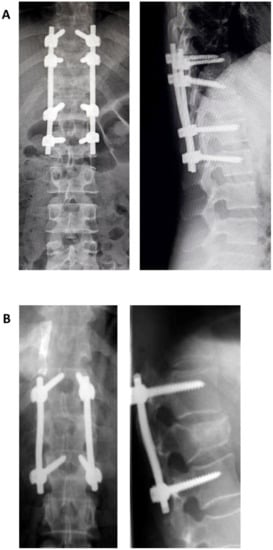

In 1983, Denis described the three columns system, which divides the Holdsworth anterior column in two, resulting a middle column which consists of the posterior half of the vertebral body, intervertebral disk and PCL (Figure 2). The middle column allows for a good differentiation between compression fractures that affect only the anterior column and burst fractures that involve both anterior and middle columns. Denis classifies thoracolumbar lesions as minor lesions—lesions of the transverse apophysis, spinous process, and isthmus (pars interarticularis) and major lesions—compression fracture, burst fracture, flexion-distraction injury (seat-belt injury), and fracture-dislocation [24]. Lesions are considered unstable if at least two columns are involved (e.g., a compression fracture with comminution is stable; a burst fracture with comminution produced by axial loading and compression of the vertebral body is unstable; the seat belt fracture that is the result of flexion and involves all three columns is unstable; a luxating fracture that involves all three columns and is a result of complex mechanisms of compression and rotation, is unstable). This classification has a series of disadvantages [25]. It does not evaluate the status of PCL that can lead over time at progressive instability, classifies all comminutive fractures as unstable (two columns involved), overlooks the neurology and provides no treatment guidelines.

Figure 2. Schematic representation of Denis’ three column concept.